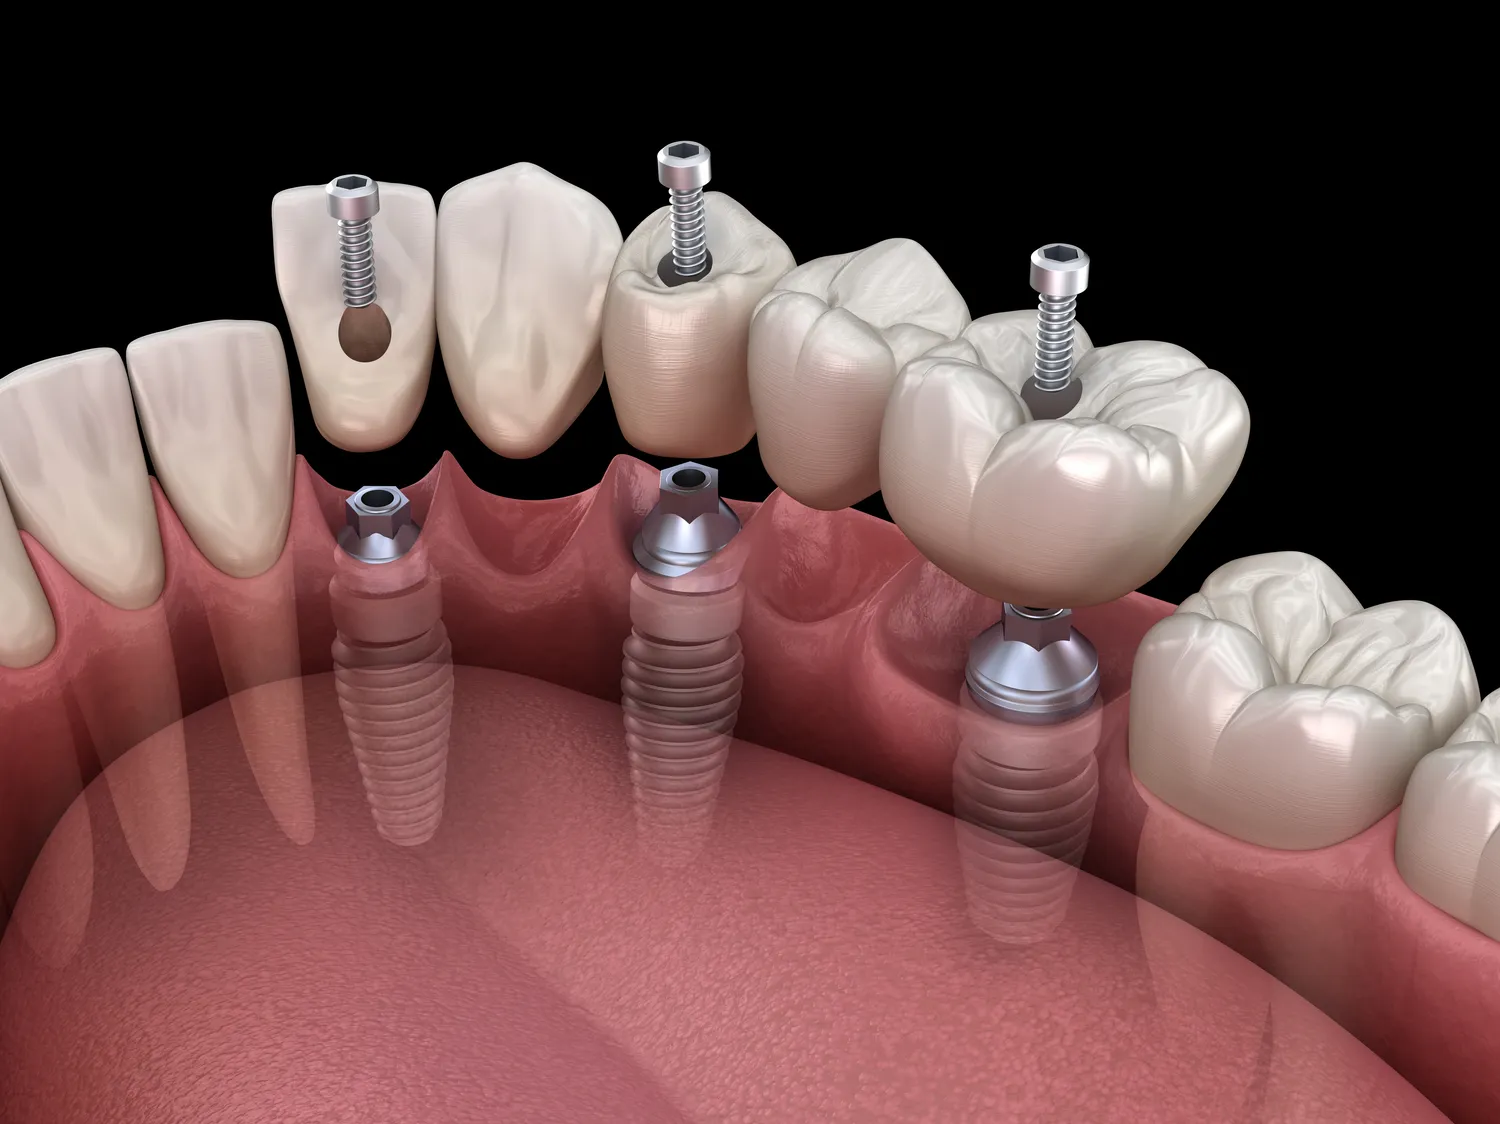

Proces Zęby w jeden dzień w Kołobrzegu składa się z kilku kluczowych etapów, które zapewniają efektywność oraz komfort pacjenta. Pierwszym krokiem jest konsultacja stomatologiczna, podczas której lekarz ocenia stan uzębienia oraz przeprowadza szczegółowe badania diagnostyczne. Na podstawie zebranych informacji tworzony jest indywidualny plan leczenia, który uwzględnia potrzeby oraz oczekiwania pacjenta. Następnie następuje etap przygotowania do zabiegu, który obejmuje wykonanie skanów 3D jamy ustnej oraz projektowanie nowych zębów przy użyciu technologii CAD/CAM. W dniu zabiegu lekarz przystępuje do usunięcia uszkodzonych lub chorych zębów oraz wszczepienia implantów dentystycznych. Po zakończeniu tej procedury następuje montaż tymczasowych koron lub mostków, które pozwalają pacjentowi na normalne funkcjonowanie aż do momentu wykonania ostatecznych uzupełnień protetycznych.

W zabiegu Zęby w jeden dzień w Kołobrzegu wykorzystywane są nowoczesne technologie, które znacząco podnoszą jakość leczenia oraz komfort pacjentów. Jednym z kluczowych elementów jest skanowanie 3D, które pozwala na dokładne odwzorowanie struktury jamy ustnej pacjenta. Dzięki temu lekarze mogą precyzyjnie zaplanować cały proces leczenia, co minimalizuje ryzyko błędów oraz zwiększa efektywność zabiegu. Kolejną innowacją jest technologia CAD/CAM, która umożliwia projektowanie i produkcję koron oraz mostków dentystycznych bezpośrednio w klinice. To oznacza, że pacjenci nie muszą czekać na wykonanie uzupełnień protetycznych w laboratoriach zewnętrznych, co znacznie przyspiesza cały proces. Warto również wspomnieć o zastosowaniu implantów dentystycznych najnowszej generacji, które charakteryzują się wysoką biokompatybilnością oraz trwałością. Dzięki tym technologiom pacjenci mogą cieszyć się estetycznym i funkcjonalnym uśmiechem już w ciągu jednego dnia, co jest ogromnym atutem tego typu leczenia.